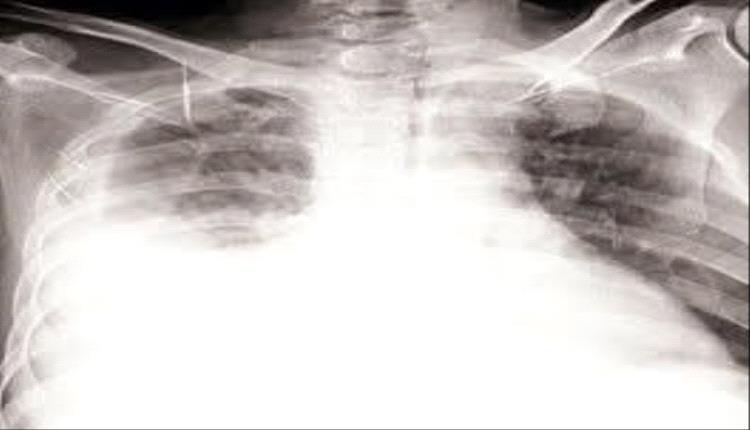

وأظهرت الأشعة وجود تجمع سوائل في الجنب الأيمن، فتم ترقيده وسحب السائل وإعطاؤه مضادات حيوية واسعة الطيف، لتحسن حالته مؤقتاً. غير أن الأعراض عادت بعد أسبوع، وأظهرت الأشعة مجدداً تجمع السوائل، لكنه رفض إعادة السحب، ثم توجه إلى الطبيب وهاج المقطري.

وجاءت نتيجة الخزعة مؤكدة لإصابته بـ السل الجنبي (Pleural Tuberculosis) رغم سلبية كل الفحوصات السابقة، ليتم تحويله إلى مركز الدرن وبدء العلاج الخاص بالسل، ومع مرور شهر ونصف بدأ التحسن يظهر عليه بوضوح.